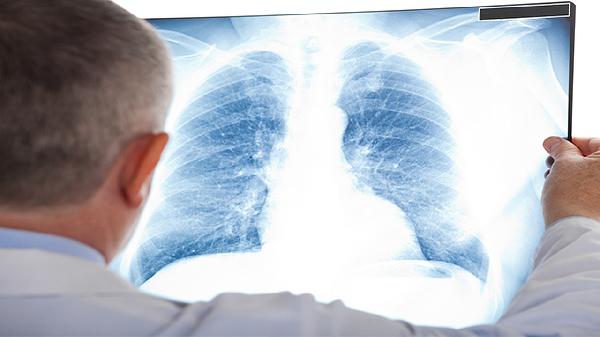

肺癌早期症状多不典型,多数表现为呼吸系统症状,部分患者可能出现全身症状。建议出现上述症状特别是持续时间较长或进行性加重时,及早进行低剂量螺旋CT等检查。长期吸烟者、有肺癌家族史、长期接触致癌物等高危人群应定期体检。日常生活中应避免吸烟及二手烟,减少厨房油烟吸入,保持良好的室内通风,注意劳逸结合,适当进行体育锻炼增强体质。